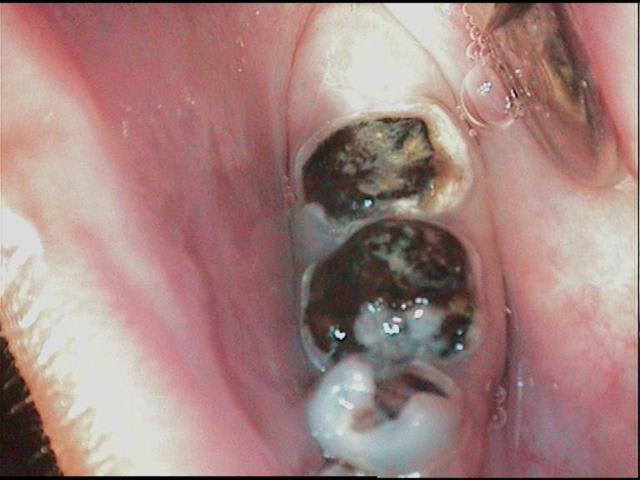

13 ans, je vous livre en vrac et dans n'importe quel sens

je m'en vais donc naviguer quelques temps entre pulpites et nécroses, calmer les pleurs, resorber les granulomes, ré équilibrer le "risque carieux"

j'ai passé les détails, aucune dent indemne de toute manière, tout est comme ça , les inc md itou

techniquement je dois etre loyal, les photos font reculer, j'ai reculé aussi en bouche, mais c'est plus impressionant au premier abord, dans le détail tout peut se jouer comme le montre cette radio

alors: les pulpites et granulomes en prems, ensuite les endos inévitables, ensuite des verre iono ou eugenates partout, ré équilibrer le risque et motiver, ensuite caler l'occlusion avec les 8 pm dans un premier temps(parceque là j'y pige rien) ensuite l'ortho (parceque là c'est pas présentable)enfin toutes ces sortes de chose quoi...